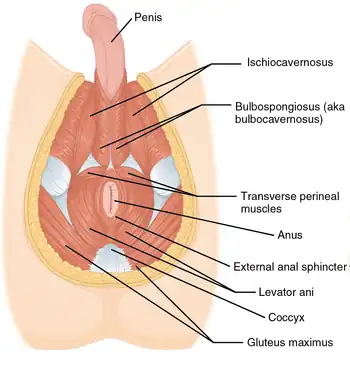

Muscles of male perineum. (Urogenital triangle is roughly equal to top half of diagram.) | |

The urogenital triangle is the area bound by a triangle with one vertex at the pubic symphysis and the two other vertices at the iliac tuberosities of the pelvic bone.

Components

As might be expected, the contents of the urogenital triangle differ greatly between the male and the female. Some of the components include:[1]

- Posterior scrotal nerves / posterior labial nerves

- Urethra

- Bulbourethral gland / Bartholin's gland

- Muscles

- Crus penis / clitoral crura

- Bulb of penis / vestibular bulb

- Urogenital diaphragm

- Muscular perineal body

- Superficial and deep perineal pouch

- Blood vessels and lymphatics